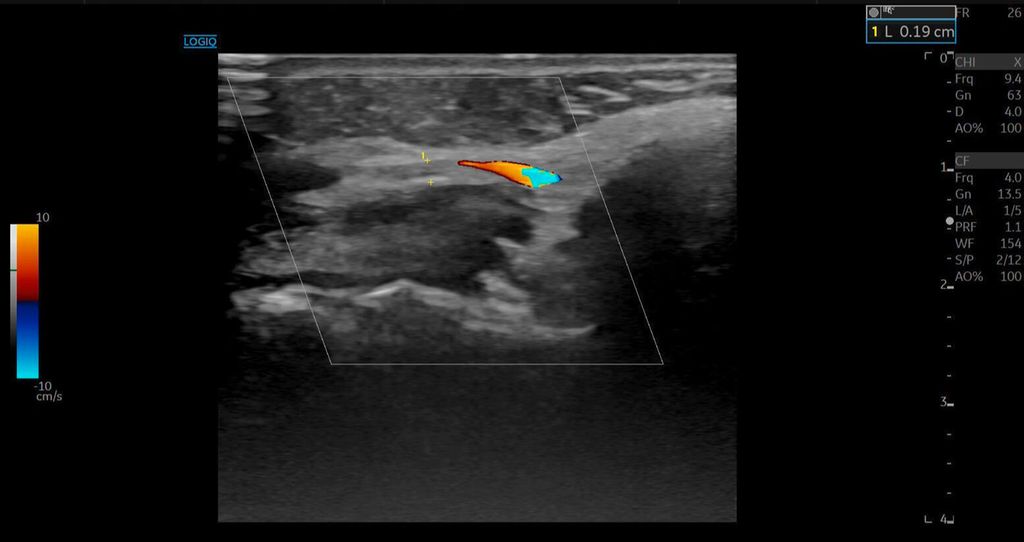

Bei der Erstvorstellung in unserer Praxis zeigten sich eine ausgeprägte Livedo racemosa der Nase sowie ischämische Verfärbungen der linken Wange mit sichtbarer Epidermiolyse. Eine Duplexsonografie ergab eine Hypervaskularisation der Nasenwurzel, ein Hyaluron-Depot sowie Zeichen einer verminderten Mikrovaskularisation («quiet zone») im Bereich der A. angularis.

Die A. facialis imponierte beim Austritt im Bereich des Musculus masseter (oberhalb der Kieferlinie) vasospastisch mit einem maximalen Durchmesser von 1mm. Die abgeleitete systolische Spitzengeschwindigkeit betrug trotz der bestehenden Ischämie 20cm/s, ohne enddiastolische Komponente, was auf eine weitere periphere Vasokonstriktion hindeutete (Abb. 2 und 3).